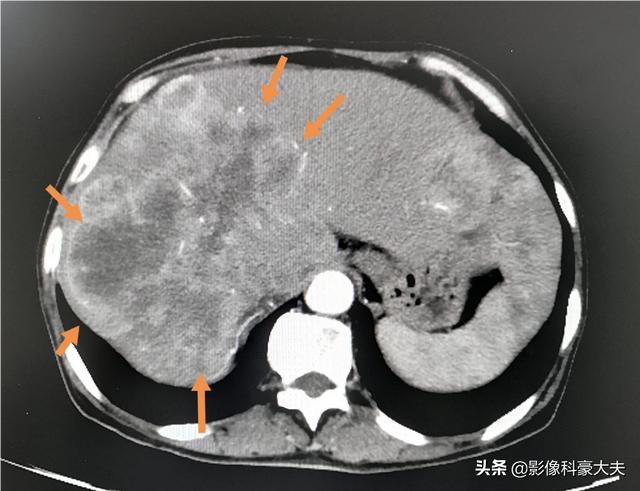

3.重要臓器への転移

がん細胞は恐ろしいもので、脳転移や肝転移など、血管やリンパのあるところならどこにでも転移する。

このような巨大な肝転移が多発した場合、コントロールできなかったり、治療に反応しなかったりすると、短期間で進行する可能性がある。

進行した肺がんの多くは、肝臓、脳、骨に転移し、臓器不全に至ることがある。

進行した肺がんは、体内のさまざまな臓器に多発転移を起こすことがある。 肺がんは脳、肝臓、骨格椎体系に転移することが多く、脳転移は頭蓋内圧亢進症を引き起こすことがある。 脳のスペースが限られているため、がん細胞が増殖すると脳ヘルニアや頭蓋内圧亢進症を引き起こし、生命を脅かすことになる。椎体転移は、病的骨折や神経の圧迫を引き起こし、麻痺や死に至ることもある。多発性肝転移は、肝機能障害や肝不全を引き起こす可能性があります。

4.腫瘍転移、多臓器不全:肺癌の末期には様々な臓器への転移が起こり、患者に大きな苦痛を与える。肺癌患者は胸膜、脳、副腎、肝臓、骨、心膜などの臓器に転移し、多臓器不全を引き起こし、患者の死に至ることもある。